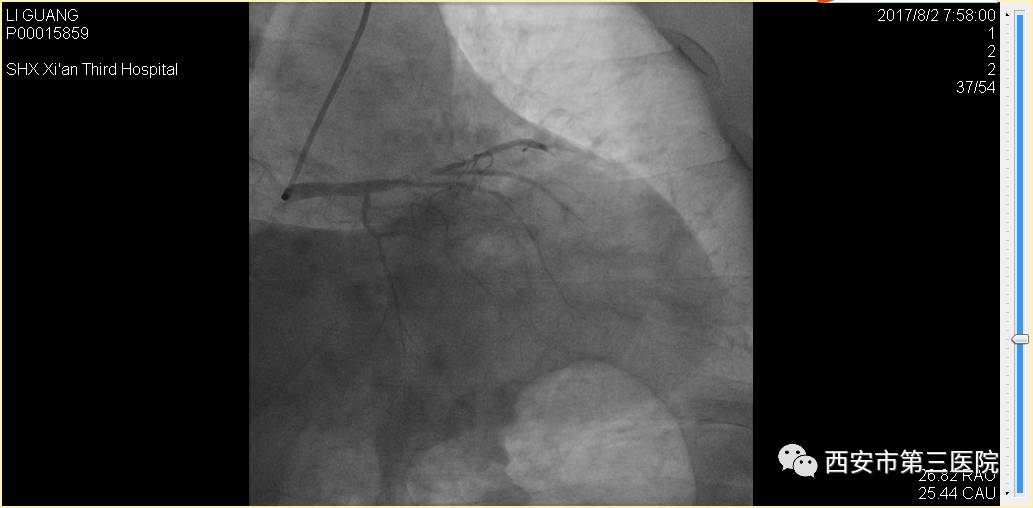

手术前